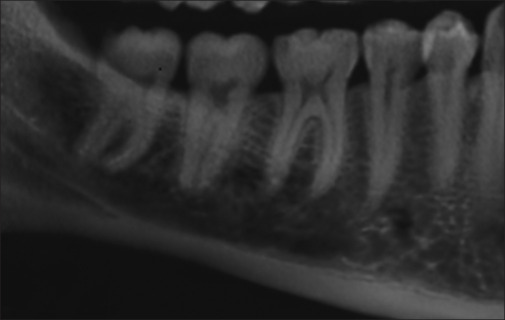

Materials and methods: In this retrospective study, 132 mandibular cone-beam computed tomography images of patients with MCI1 were evaluated. 6-point rating MCV score and CR were determined for cross-sections of the MC in the following areas: incisive canal (INC), mental foramen and canal (MF), first premolar to the third molar (1PM, 2PM, 1M, 2M, and 3M), and the corresponding edentulous areas (E1PM-E3M). 1PM was overlapped with MF in most cases. An MCV score1 (excellent visibility) and 2PM area were considered reference levels.

Results: Sex and age did not significantly affect the MCV score or CR (P > 0.05). 98.6% of the INC and 92.31%-100% of the MC were visible. The mean ± SD of the CR in the INC and MC was 0.86 (0.23) and 0.77 (0.29), respectively. The estimated difference in the mean CR was statistically significant only between the INC area and dentulous areas (P < 0.001).